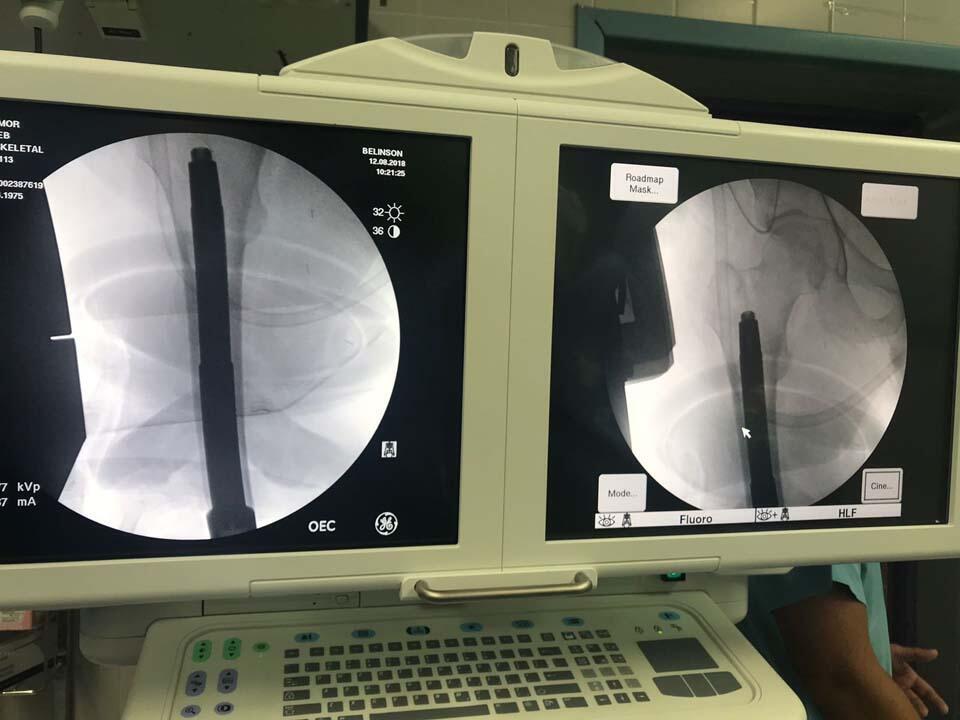

Во время операции. Фото: пресс-служба "Бейлинсон"

(Фото: пресс-служба больницы "Бейлинсон")

Операция получила название "остеоинтеграция". В ходе операции титановый стержень длиной 16 см крепится к кости больного. Свободный конец стержня выводится из культи наружу, и к нему крепится протез.